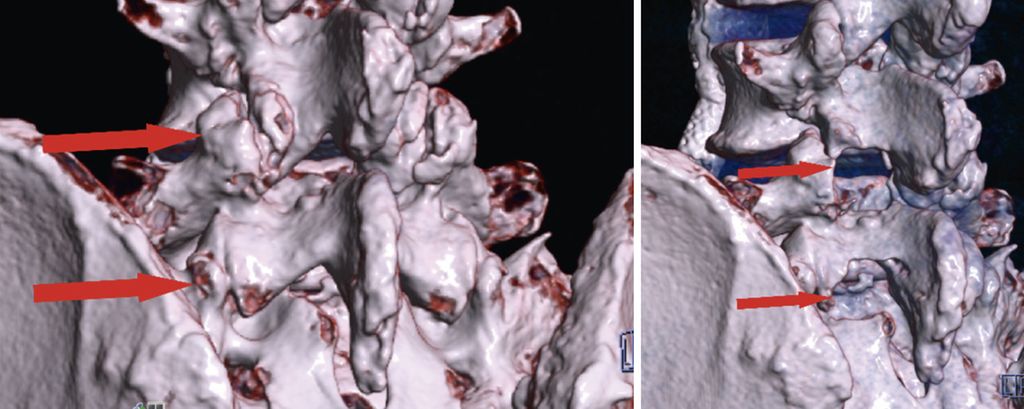

Bei zentraler Spinalkanalstenose und lateraler Rezessusstenose ermöglichen endoskopische Verfahren eine schonende und effektive Dekompression. Eingriffe können unilateral oder bilateral über die Over-the-top-Technik (ULBD) erfolgen. Randomisierte Studien belegen ein funktionell gleichwertiges Outcome im Vergleich zur offenen Dekompression, jedoch bei günstigerem Risikoprofil, kürzerem stationärem Aufenthalt und früherer Mobilisierung.13,19 Bei 161 Patienten mit lateraler Rezessusstenose konnte eine Überlegenheit der vollendoskopischen Operation hinsichtlich Operationszeit, Blutverlust, Komplikationsrate und Revisionshäufigkeit demonstriert werden.19 Am eigenen Patientenkollektiv bei 80 interlaminären vollendoskopischen Dekompressionen konnten 76% der Patienten bereits am Operationstag mobilisiert werden. Über die generellen Vorteile der spinalen Endoskopie hinaus zeigt sich, dass bestimmte Patientengruppen in besonderem Masse profitieren. Hierzu zählen adipöse Patienten, (Leistungs-)Sportler mit dem Bedürfnis nach rascher funktioneller Erholung und minimiertem Gewebetrauma sowie ältere Patienten, bei denen eine erhöhte Invasivität die Mobilisierung weiter einschränken würde und die dadurch profitieren. Abbildung 5 zeigt eine präoperative (linkes Bild) und postoperative (rechtes Bild) 3D-CT-Rekonstruktion nach endoskopischer unilateraler Laminotomie mit bilateraler Dekompression (ULBD) bei L4/5 und L5/S1 (Abb. 5).